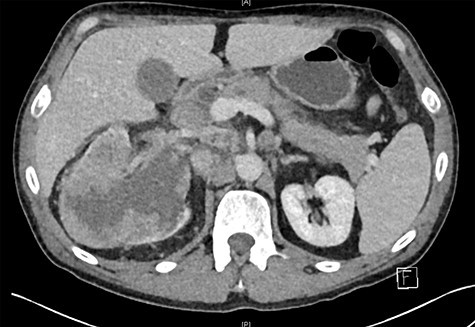

Biochemistry results revealed a lipase and bilirubin of 1105 units/L and 93 umol/L, respectively. Subsequently, a 12.5 × 11.3 cm heterogenous mass arising from the right kidney was found on a contrast enhanced computed tomography (CT) scan (Fig. 1). This mass was associated with a non-contiguous adrenal metastasis ipsilaterally and retrocaval lymphadenopathy adjacent to the pancreatic head resulting in biliary and pancreatic duct dilatation (Fig. 2). A staging CT chest with intravenous contrast was then performed revealing mediastinal lymphadenopathy suggestive of metastasis.